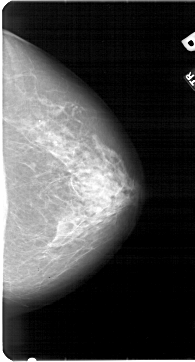

A_1954_1.RIGHT_CC

RIGHT_MLO LINES 5491 PIXELS_PER_LINE 3001 BITS_PER_PIXEL 12 RESOLUTION 43.5 NON_OVERLAY